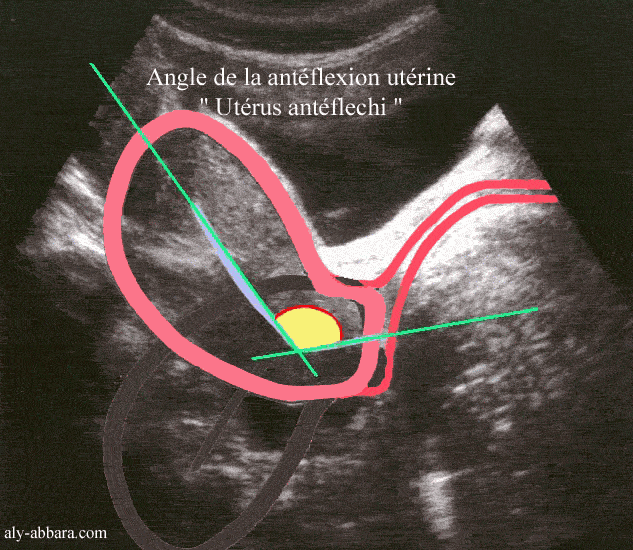

Гинекология и здоровье: антеверсио матки — что это такое?